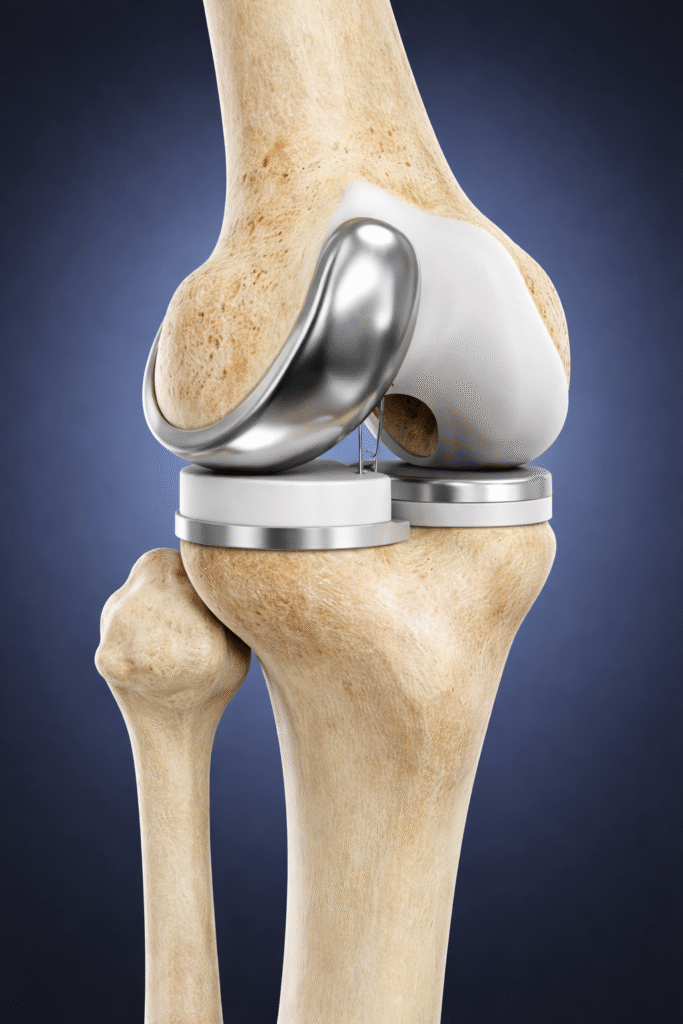

What is Microplasty – Partial Knee Replacement?

Microplasty Knee Surgery in Ahmedabad is a minimally invasive procedure where only the worn-out cartilage and bone are replaced with an implant while preserving healthy knee structures.

How Microplasty Surgery is Performed

Pre-Surgical Evaluation

Diagnosis using X-rays or MRI to confirm localized arthritis.

Small Incision

Minimally invasive approach to access the affected compartment.

Damaged Tissue Removal

Only worn cartilage and bone are replaced.

Implant Placement

A precision-fit implant is inserted to restore alignment and function.